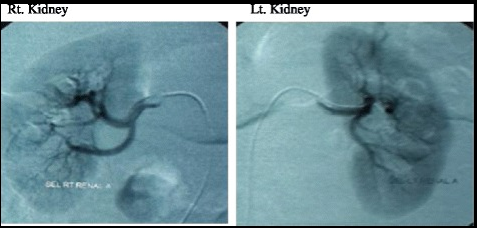

间充质干细胞外泌体治疗慢性肾脏疾病

慢性肾脏疾病(CKD)是一种进行性和不可逆的疾病,在肾功能下降到特定临界值后发生。慢性肾脏疾病会伴随着进行性肾小管间质纤维化,最终导致终末期肾病(ESRD)。

图片来源[2]

2016年的一项研究将来间充质干细胞的外泌体应用于治疗慢性肾脏疾病,并发现了间充质干细胞外泌体对慢性肾脏疾病的治疗作用,而这可能是循环中抗炎细胞因子增多而促炎细胞因子减少引起的[2]。